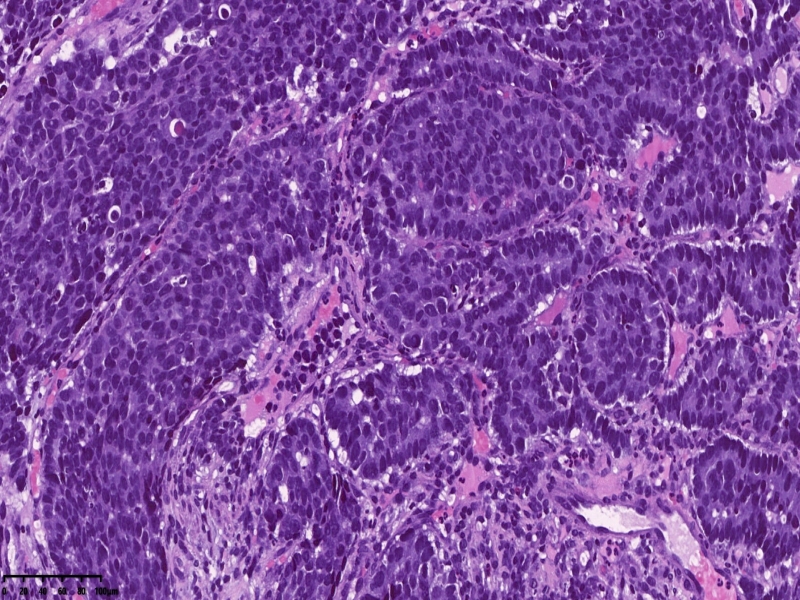

镜下所见:胃粘膜组织数块,炎症背景,其中3块固有层内可见细胞团,瘤细胞排列呈条索状迂回后呈巢状,巢的边缘瘤细胞呈栅栏状。细胞形态似柱状。

第一感觉考虑神经内分泌肿瘤?会诊考虑低分化腺癌。以前也遇到一个类似病例,贲门口占位,初步考虑神经内分泌肿瘤,但是神经内分泌标记均为阴性,最后考虑低分化腺癌。

免疫组化:ki67增值指数较高约80%,CK7VillinCAM5.2、CEA+,CA19-9CDX-2部分+

神经内分泌标记S100-,只做了这一个